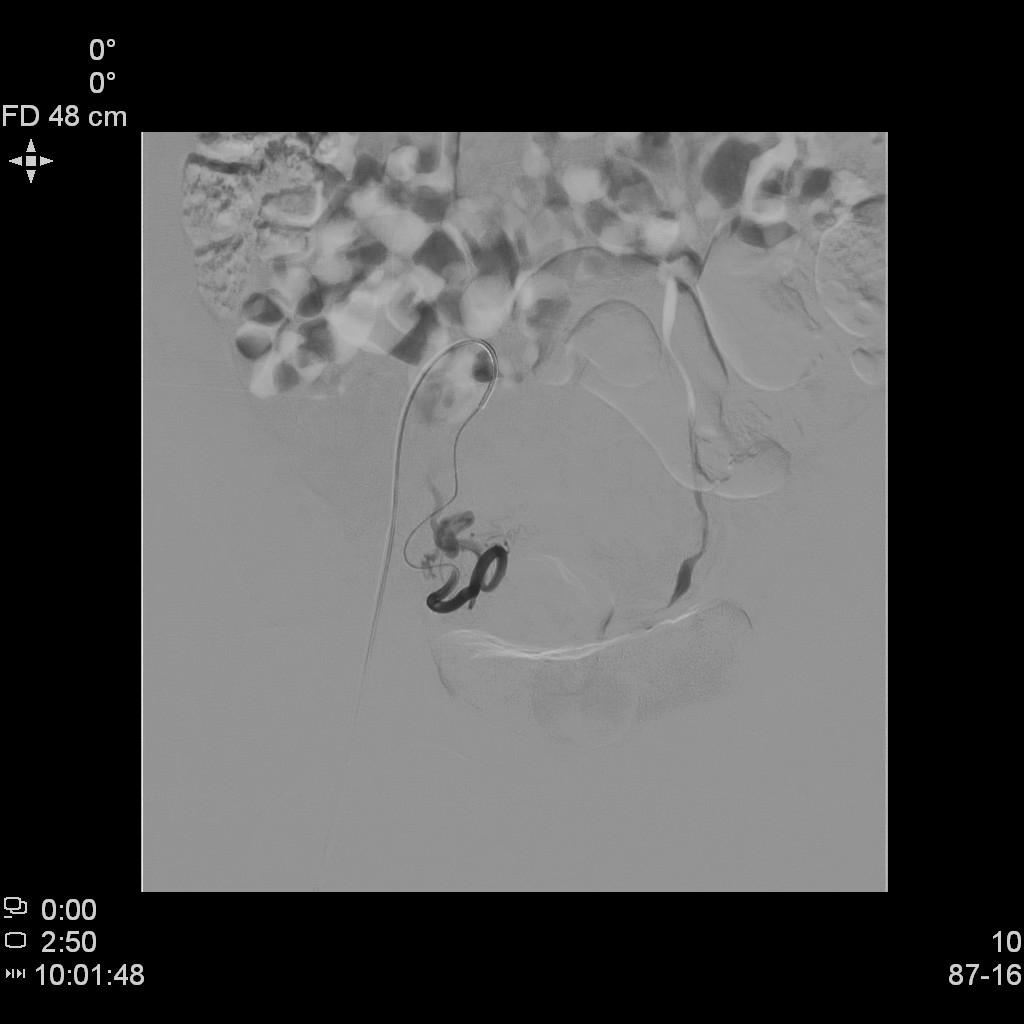

- DSA下行双侧子宫动脉栓塞治疗。

左侧子宫动脉造影

右侧子宫动脉造影